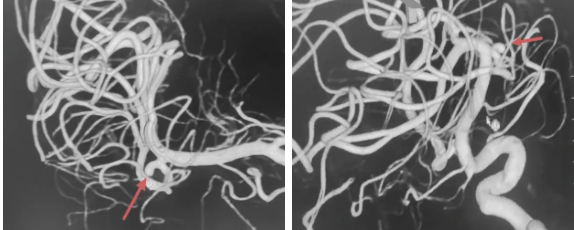

1. 术前评估,基线造影

DSA三维重建示:大脑中M2分叉部可见一动脉瘤,瘤体不规则

2. 方案确定,策略规划

大脑中动脉M2段,被称为脑血管的“交通要道”,是分叉后重要穿支供血区。传统开颅夹闭创伤大、暴露困难,牵拉脑组织后认知功能障碍风险增加。此外,M2段动脉瘤多为宽颈或分叉部动脉瘤,单纯栓塞易复发。故经综合评估瘤体位置,瘤颈宽度等,确定手术方案“Atlas支架植入术+动脉瘤弹簧圈栓塞术”。